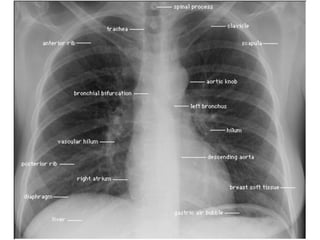

コミュニケーションに

気

胸

縦

横

骨

軟

チュー

気管

胸腔

縦隔

横隔膜

軟部組織

チューブ